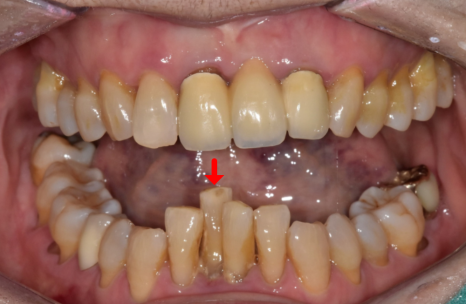

오늘은 70대 환자분의 솟구치고

흔들리는 치아 해결 과정을

케이스를 통해 설명해 드릴게요.^^

2년 사이 치아가 위로 솟고

흔들리게 된 이유

2년 전만 해도 뼈 상태가 양호하고

흔들림도 없으셨던 분인데,

2년 후 다시 뵙게 된 환자분은

아래 앞니 2개가 눈에 띄게 솟구치고

심하게 흔들리는 상태였습니다.